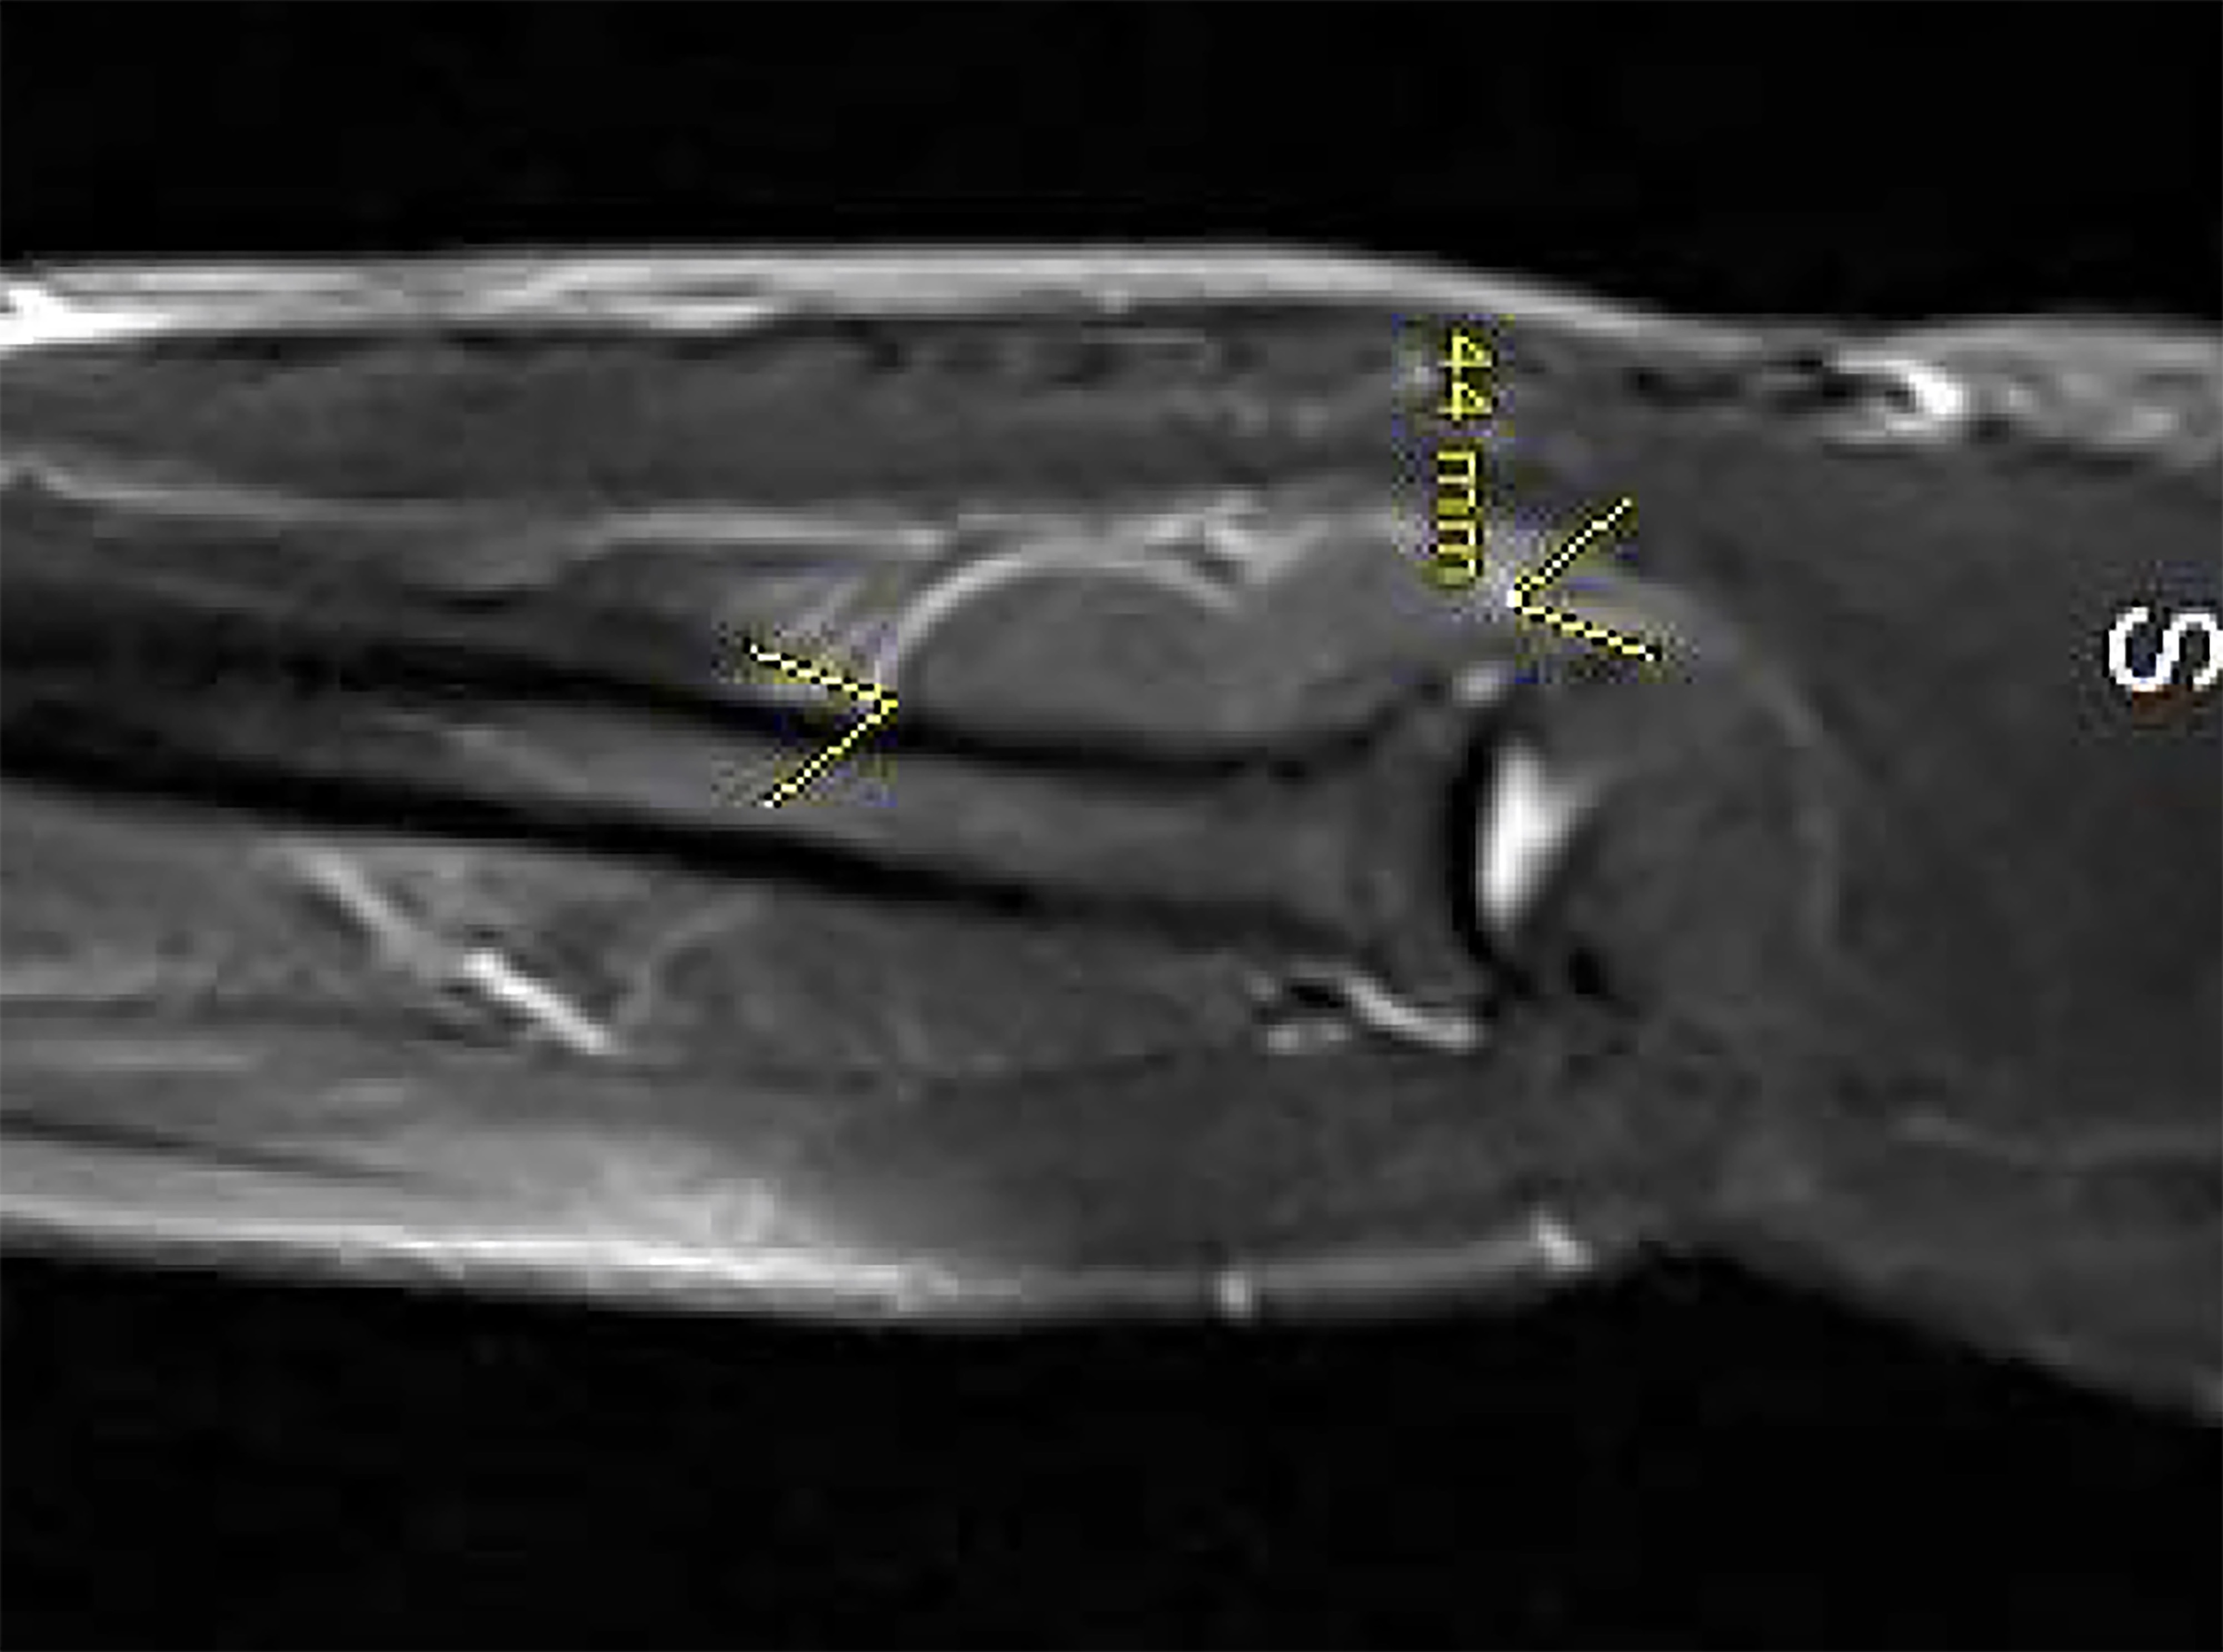

A 42-year-old, right-hand dominant male presented with several months of progressive right upper extremity motor weakness. The patient first noticed weakness and then the complete loss of extension of the long finger and ring finger, followed by the loss of extension of the small finger, and eventually weakness of the thumb and index finger extension (Figure 1). The patient’s wrist extension was intact, and there were no palpable masses or inciting traumatic events. Electromyography (EMG) and nerve conduction studies (NCS) were ordered and demonstrated posterior interosseous nerve (PIN) involvement. Magnetic resonance imaging (MRI) of the right forearm showed a well-circumscribed mass over the radial head. The patient was taken to the operating room for excision of the mass. Intraoperatively a 44 mm x 27 mm x 16 mm lipoma located deep against the PIN, causing obvious clinical PIN narrowing, was excised. All branches of the radial nerve were spared, and a complete decompression of the PIN was performed. The patient had progressive and continued recovery of finger extension postoperatively. (Figure 1)

The best tools to discern the etiology of radial nerve palsy are an astute history and physical exam, as the loss of motor function depends on the level of radial nerve involvement. In this case, the patient had intact elbow and wrist extension, indicating intact innervation to the triceps muscles and wrist extensors (ECRB, extensor carpi radialis longus ) which effectively ruled out a brachial plexus or proximal radial nerve injury. The patient’s progressive loss of finger extension and absence of distal sensory symptoms pointed to a progressive process distal to the origin of the PIN. At this point, adjunct studies such as MRI and radiographs are indicated to rule out underlying masses, fractures, dislocations, and foreign bodies. In this case, the MRI demonstrated a sizeable lipoma (Figure 2, Figure 3). Suspected radial nerve paralysis from a penetrating injury follows a slightly different algorithm than in penetrating trauma and should be explored urgently. In these cases, adjunct imaging such as MRI or arteriograms may be useful prior to exploration whereas electrodiagnostic studies prior to exploration are unnecessary.4 Early EMG and NCS are unable to differentiate between nerve injuries that will or will not heal spontaneously and should be reserved for persistent nerve paralysis beyond 6 to 8 weeks.1 By 12 weeks, the presence of motor unit potentials can differentiate injuries that will require surgery or heal spontaneously.

The differential diagnosis for forearm masses is broad. Reported masses causing PIN compression include lipomas, liposarcomas, ganglion cysts, intraneural hemangiomas, and tumors of nerve origin.2,5 As previously mentioned, an MRI serves as a useful adjunct in determining the cause of nerve palsy and may assist with diagnosing masses when detected. Importantly, MRIs prior to surgery can help distinguish between benign and malignant masses, which may alter surgical planning, margins, and reconstruction. Although effective in diagnosing masses, an MRI is not definitive. A recent study on upper extremity lesions found an overall sensitivity of MRI of 75% compared to lesion pathology after excision, with improved radiologic diagnosis of ganglions and lipomas compared to malignant lesions.6 Pertinent to this case, lipomas characteristically demonstrate MRI signal characteristics identical to subcutaneous fat, which include hyperintense T1 and T2 signals with hypointense short-TI inversion recovery (STIR) signal (Figure 2, Figure 3).6 Heterogeneity within the lesion should raise the possibility of liposarcoma as a possible diagnosis. In contrast, ganglion cysts typically present with hypointense T1 signal and hyperintense T2 and STIR signals. An MRI with gadolinium contrast is useful for detecting and differentiating between possible vascular lesions.